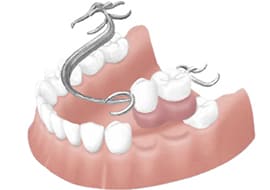

他の治療との比較

歯を失った場合に機能や見た目を回復する為の方法としてブリッジ、入れ歯、インプラントの3つの治療の選択肢があります。

これらの治療法には利点もあれば欠点もあります。ここではこれら3つの治療法について比較紹介します。